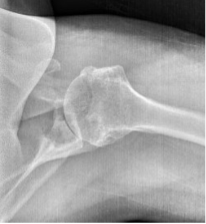

BH is a right hand dominant 70-year-old female, who is retired and moderately active. She presents with 8 months of progressively worsening left shoulder pain affecting her ADLS, sleep and recreational activities. She is 10 years s/p a right anatomic total shoulder arthroplasty. Radiographs and advanced imaging reveal glenohumeral joint advanced degenerative joint disease with an intact rotator cuff. Preoperative planning reveals a native 3 degrees of retroversion with 0 degrees of inclination. As she was extremely happy with the fully functional contralateral shoulder she has enjoyed for the past decade, she was interested in the same solution – an anatomic total shoulder arthroplasty.